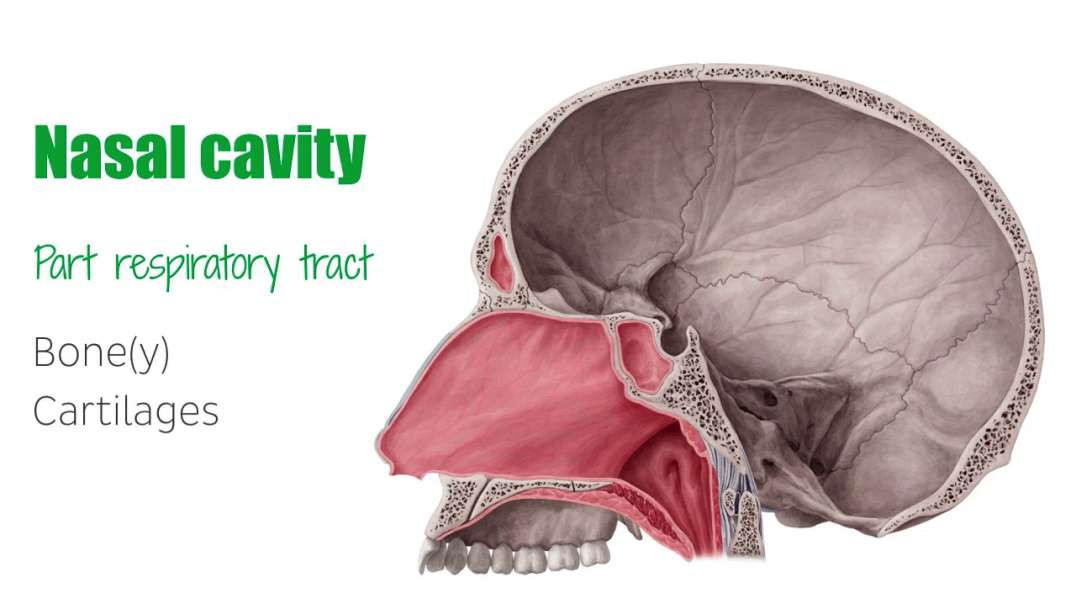

Armando - Clinical Anatomy - Nasal Cavity and Sinuses

Armando - Clinical Anatomy - Nasal Cavity and Sinuses